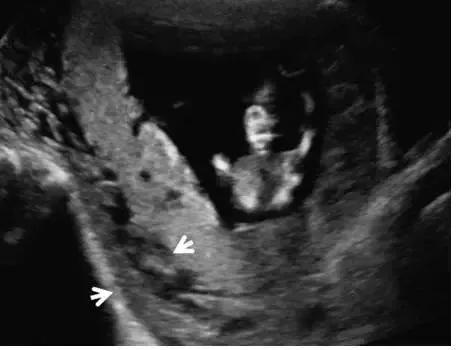

超声最早可在孕 6 周(经阴道超声)或孕 10 周(经腹部超声)显示出胎盘,表现为妊娠囊周围的薄层环状高回声。妊娠 12~13 周时,多普勒超声可显示绒毛血流。孕 14~15 周时,胎盘已充分发育,表现为显著的高回声。此时,也可看到由蜕膜、肌壁、子宫血管等组成的胎盘后复合体(图 1)。

图 1 孕 12 周时的正常胎盘矢状面,其后可见低回声的胎盘复合体(小箭头)